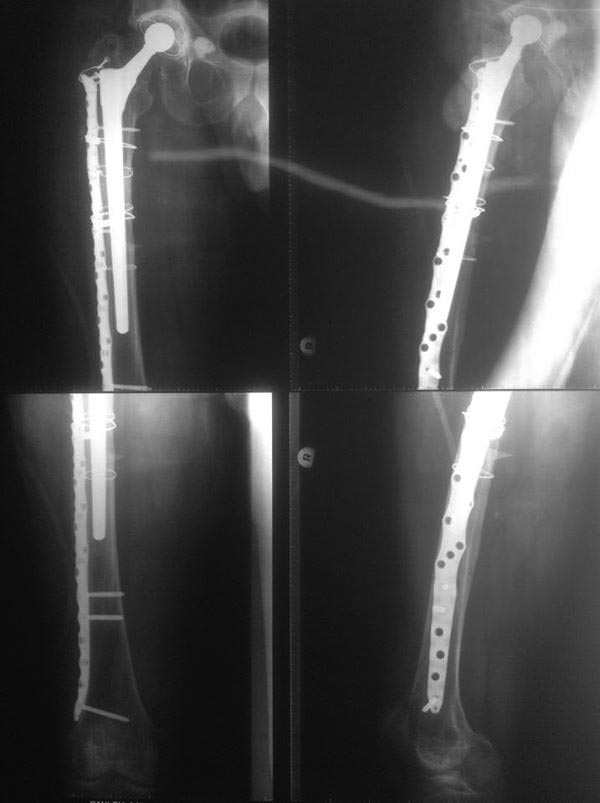

Re: Перипротезный перелом

А какова здесь надежность фиксации ножки в гвозде? В ситуации с оскольчатым характером перелома и его масштабами верхний доступ был бы тех же размеров. Цемент в любом случае полагается удалить. Операция выполнялась в соответствии со всеми принципами АО, ревизия перелома ad oculus подтвердила верность выбора хирургической тактики, при этом избежав нанесения дополнительной травмы доступом через коленный сустав))

Надежность, если все правильно сделано, как минимум достаточная для любых нагрузок. Не понял насчет "был бы тех же размеров" - это и есть оскольчатый перелом, вот снимок до операции. Никаких верхних доступов, все закрыто. Принципы АО - вещь переменная, в конце 2013 г. издана аошная книжка про перипротезные переломы, там уже есть про эту методику. Цемент иногда действительно приходится удалять, но мы уже в 3 случаях смогли сделать без обнажения конца ножки, вытаскивали кусочки цемента через доступ для гвоздя. Не "ревизия ad oculus" подтверждает верность тактики, а результат. Представлен хороший непосредственный результат, будем надеяться, в дальнейшем он сохранится. А тактика верная - не обязательно одна. Могут быть и три првильных.

в этом случае перелом перипротезный на уровне эндопротеза с нестабильностю ножки. Это требует замены ножки. ПЛАСТИНА в любом случае требует большей инвазии. Здесь я за ножку вагнера.

Вот и было сделано нечто типа длинной ножки. Только закрыто и с запиранием.

И это правильно.

Предлагаю вернуться к первоначальному снимку.

Допустим, мы не трогаем зону перелома, делаем закрыто, бережем мягкие ткани.

А коленный сустав?)

Существует ли та или иная доказательная база критериев определения стабильности соединения - "ножка-гвоздь"?

Какова вероятность того, что при нахождении на одной линии с переломом ножка, забитая в гвоздь будет сохранять триаду "ось-длина-ротация" в случае концентрации нагрузки на импланте при отсутствии контакта/фиксации отломков?

В смысле если посмотреть на первоначальный снимок - я бы не рискнул оперировать закрыто, без тщательного удаления цемента и фиксации лишь пятой дистальной части ножки в установленном через коленный сустав гвозде.

Михаил., без нашего опыта последних лет, может, и я бы не рискнул. С коленным суставом проблем не возникает. "доказательная база критериев определения" - просто прекрасно, запишу. Стабильность после сколачивания уже в десятках случаев эмпирически проверена. И "при нахождении линии" все хорошо. А после сращения можно сделать планово ревизию, и поставить первичный компонент.

Снимки красивые, но "люди ходят не на снимках, люди ходят на ногах". Поэтому не лишними были бы подобности типа возраста пациента, его уровня активности, хода операции (длительность, кровопотеря), ну и всякие другие небезинтересные вещи.

Не являюсь спецом по перипротезным переломам, но у нас как правило или остеосинтез или ревизионная ножка - что послужило здесь поводом сочетать оба метода?

"Операция выполнялась в соответствии со всеми принципами АО" - судя по количеству серкляжей вы с этой фразой немного погорячились. Кстати тоже: пластина позволяет вводить винты спереди и сзади от ножки протеза - почему предпочли не винты, а проволоку?